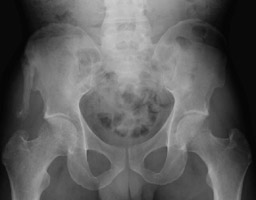

- Click on the image for a larger versionBAP radiograph of the pelvis. This shows a prior healed avulsion fracture of the anterior superior iliac spine.